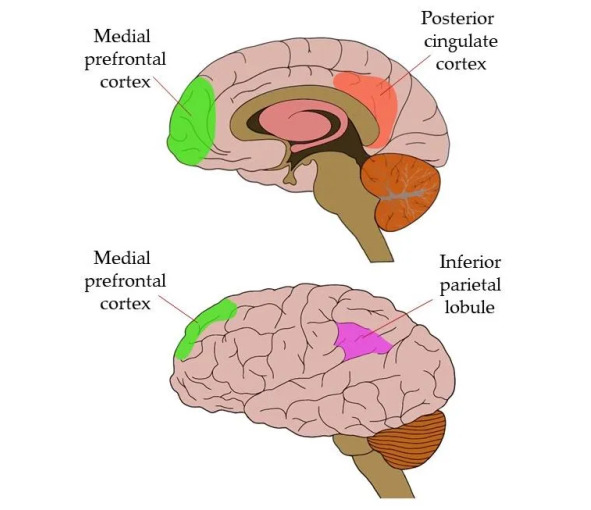

В некоторых работах дефолт-система называется «сетью пассивного режима работы мозга», потому что исследователи наблюдали ее активную работу, только когда человек отдыхал, но последние наблюдения указывают на то, что она активно участвует и в принятии решений. Дефолт-система включает в себя: часть префронтальной коры (вентромедиальный и дорсомедиальный участки лобных долей), латеральную теменную кору, кору задней части поясной извилины, предклинья и энторинальную кору.